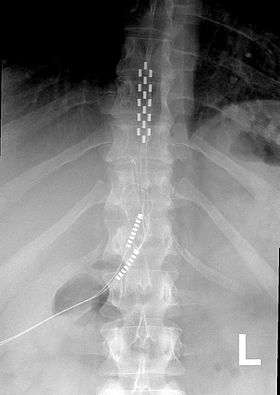

![]() Anterior view X-ray of a spinal cord stimulator (SCS) implanted in the thoracic spine |

A spinal cord stimulator is a device used to exert pulsed electrical signals to the spinal cord to control chronic pain. Further applications are in motor disorders. The lumbar spinal cord is a preferred target for the control of spinal spasticity[1][2] or augmentation of standing and stepping capabilities.[3][4][5][6] Spinal cord stimulation (SCS), in the simplest form, consists of stimulating electrodes, implanted in the epidural space, an electrical pulse generator, implanted in the lower abdominal area or gluteal region, conducting wires connecting the electrodes to the generator, and the generator remote control. SCS has notable analgesic properties and, at the present, is used mostly in the treatment of failed back surgery syndrome, complex regional pain syndrome and refractory pain due to ischemia.

The electrodes, which consist of an array of leads, could be percutaneous type or paddle type. Percutaneous electrodes are easier to insert in comparison with paddle type, which are inserted via incision over spinal cord and laminectomy.[16]

SCS procedure involves careful placement of electrodes in the epidural space, a trial period (which takes between 5–7 days), and, if the results of pain relieving was satisfactory in the trial period, anchoring the electrodes to the interspinal ligaments, positioning and implantation of the pulse generator, tunneling and connection of the connecting wires, programming the system for the special pattern of stimulation and performing required postoperative cares.[15]